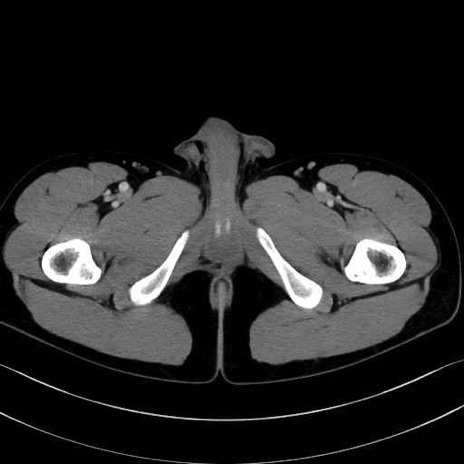

小殿筋 (Gluteus minimus)